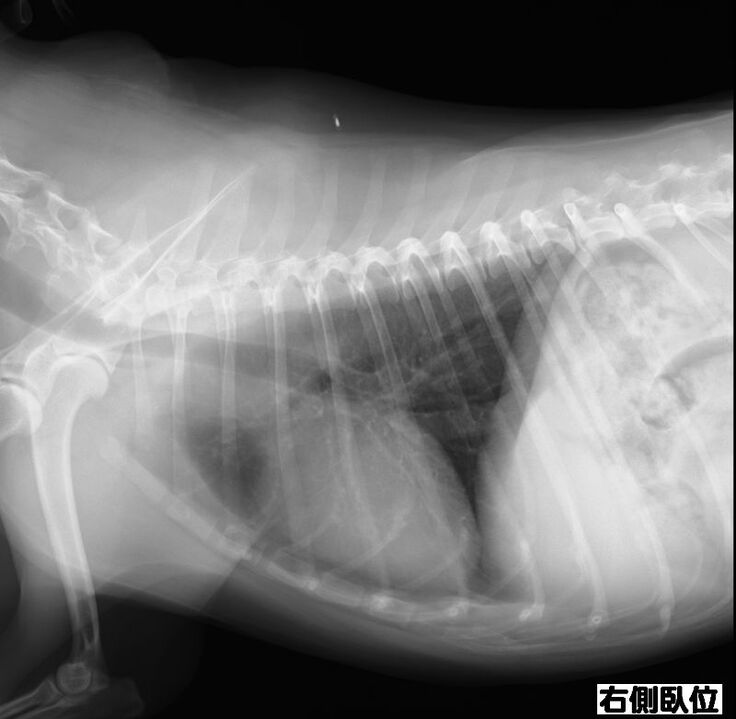

以前より下部尿路疾患で尿路結石を持っているチョコですが、膀胱にある結石が大きくなり膀胱を痛めて膀胱炎を頻繁に発症するようになりました。

膀胱炎から炎症が全身に、更には脾臓の腫瘍が確認されました。

膀胱炎の資料をご覧ください。

検査結果もかなりの異常さが分かると思います。

現在9歳のチョコですが、脾臓はいずれ摘出した方が良いと獣医師より指摘されております。まだ若いので悪性の可能性は低いと言われています。また、結石も同時に摘出をした方が良いと。

検査の結果、脾臓肥大が限界近くの爆発寸前になっていることが判明しました。

脾臓は4センチまでなってるから、いつ破裂してもおかしくない状況。